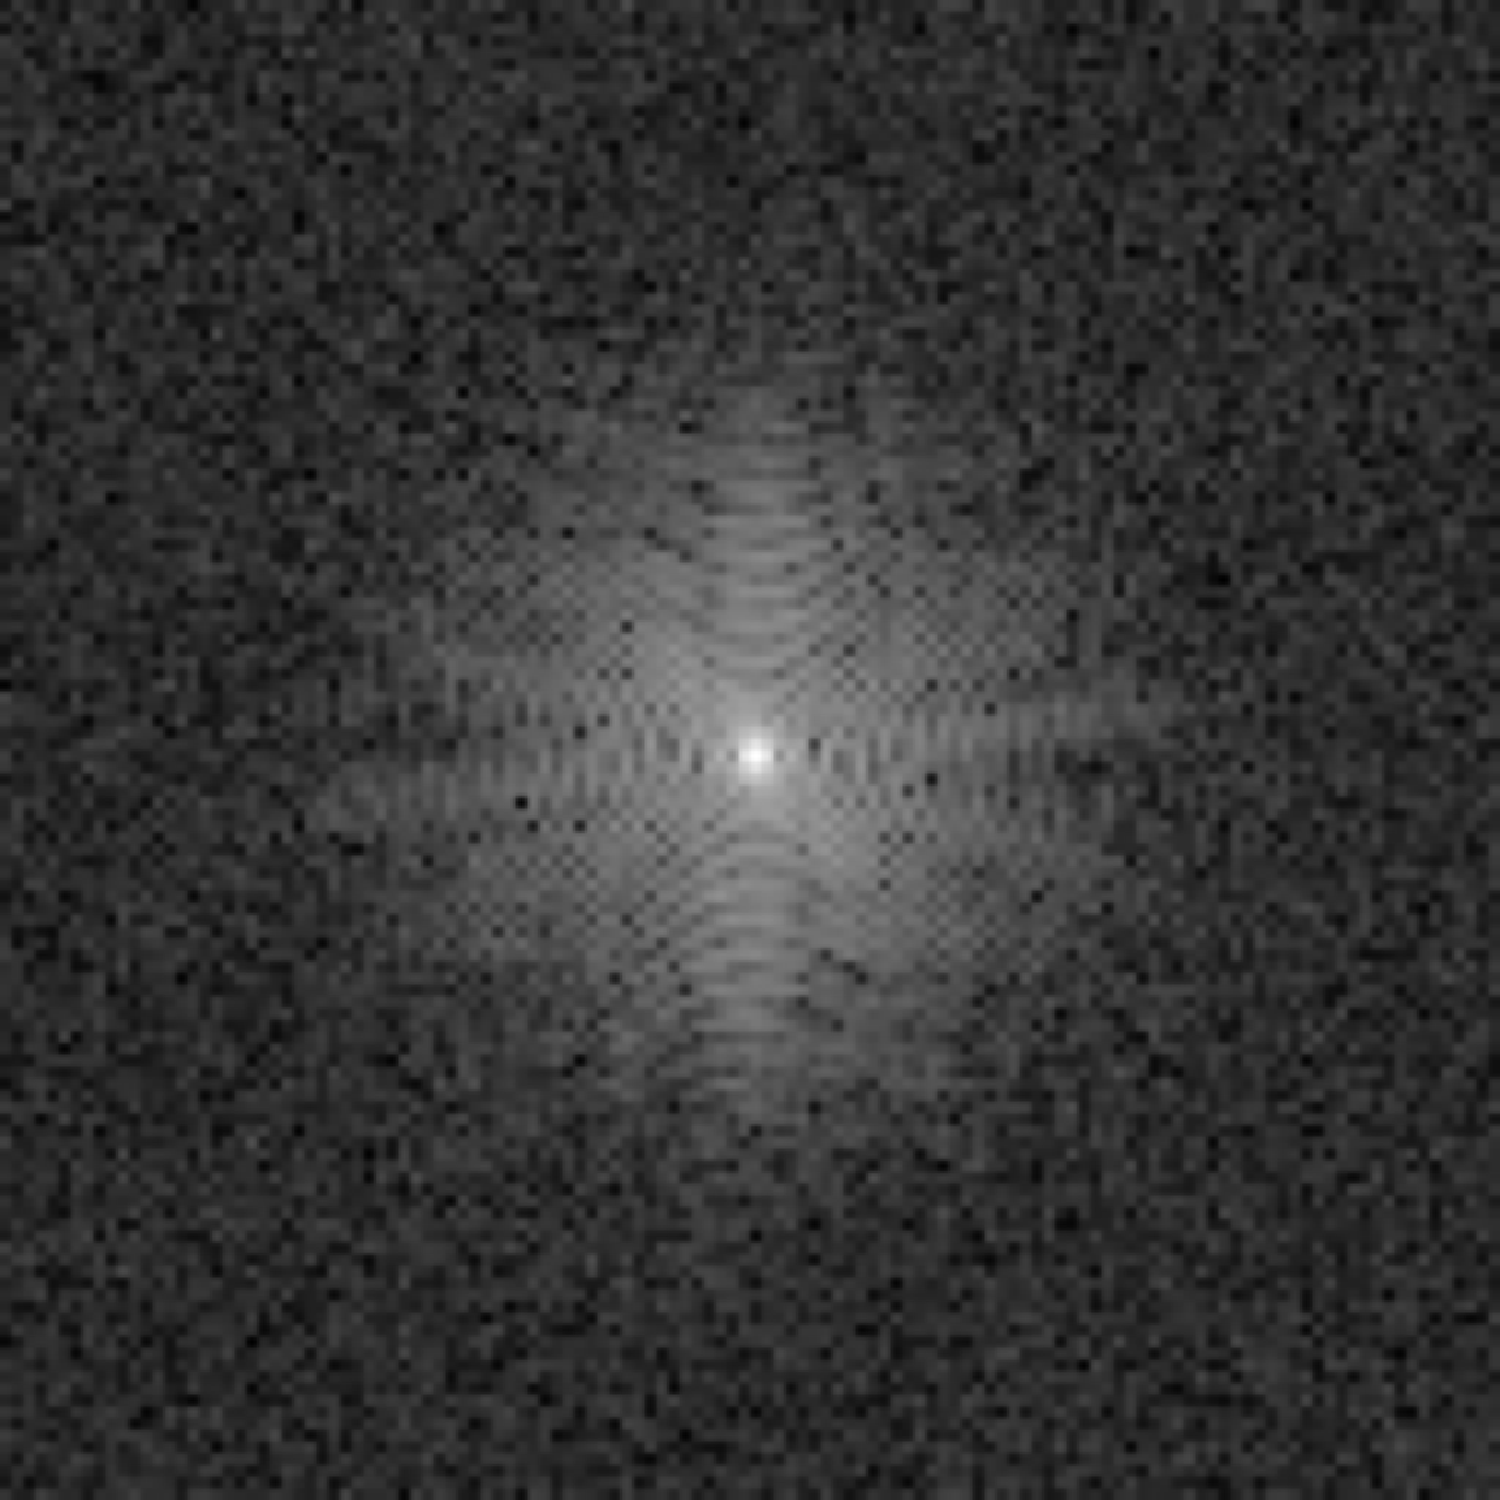

A simulation study was conducted. MR brain images in the NYU fastMRI Initiative database [11] (https://fastmri.med.nyu.edu/) were employed to form an ensemble of images that depict object properties sampled from the unknown SOM. Specifically, 3000 T1 weighted brain MR images corresponding to the magnetic field strength of 3T were selected, and these 3000 images were resized to the dimension of to be employed as real object images. Fully-sampled MR k-space data of these 3000 object images were simulated, and complex Gaussian noise were added to the k-space data. These 3000 noisy k-space measurement data formed the training dataset. An example of MR brain images, its corresponding k-space measurement data and the reconstructed image (i.e., IDFT of k-space measurement data) are shown in Fig. 2.